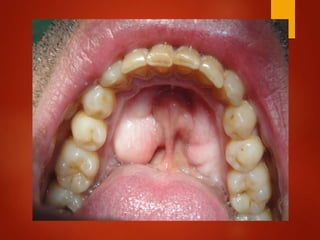

El documento es un registro médico odontológico que muestra las fechas de las visitas de un paciente al centro de salud El Raval, incluyendo exámenes y tratamientos realizados como la extracción de cálculos salivales en abril y mayo de 2012.